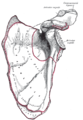

الأخرم (من اليونانية: أكروس، "الأعلى" ōmos، "الكتف"، المفرد: acromia)، هو نتوء عظمي على عظمة الكتف (لوحة الكتف). يمتد الأخرم والناتئ الغرابى جانبياً معاً فوق المفصل الحقاني العضدي. يتمفصل الأخرم مع الترقوة ليكوّنا المفصل الأخرمي الترقوي.

البنية

الأخرم يشكل قمة الكتف، وهو نتوء كبير، شكله مثلث إلى حد ما أو مستطيل، مفلطح من الخلف إلى الأمام، يبرز أوله وحشياُ، ثم يتقوس إلى الأمام و إلى الأعلى، ثم يتعلق مشرفا على التجويف الحقاني.[1]

الأسطح

السطح العلوي يتوجه لأعلى ، وإلى الوراء، ونحو الجانب الوحشي ، وهو محدب و خشن، ويتصل علي بعضه ألياف العضلة المثلثة (الدالية)، وفي بقية مداه يتغطي بنسيج تحت الجلد إنگليزية: Subcutaneous tissue. سطحه السفلي ناعم ومقعر.[1]

الحواف

الحافة الجانبية الوحشية سميكة وغير منتظمة، وهناك ثلاث أو أربع حديبات للمنشأ الوتري للعضلة المثلثة (الدالية). حافتها الوسطي الإنسية أقصر من الوحشية وهي مقعرة ، ويتصل عليها جزء من العضلة شبه المنحرفة، وفي وسطهاتقريبا سطح بيضاوي صغير للتمفصل مع النهاية الأخرمية للترقوة.[1]